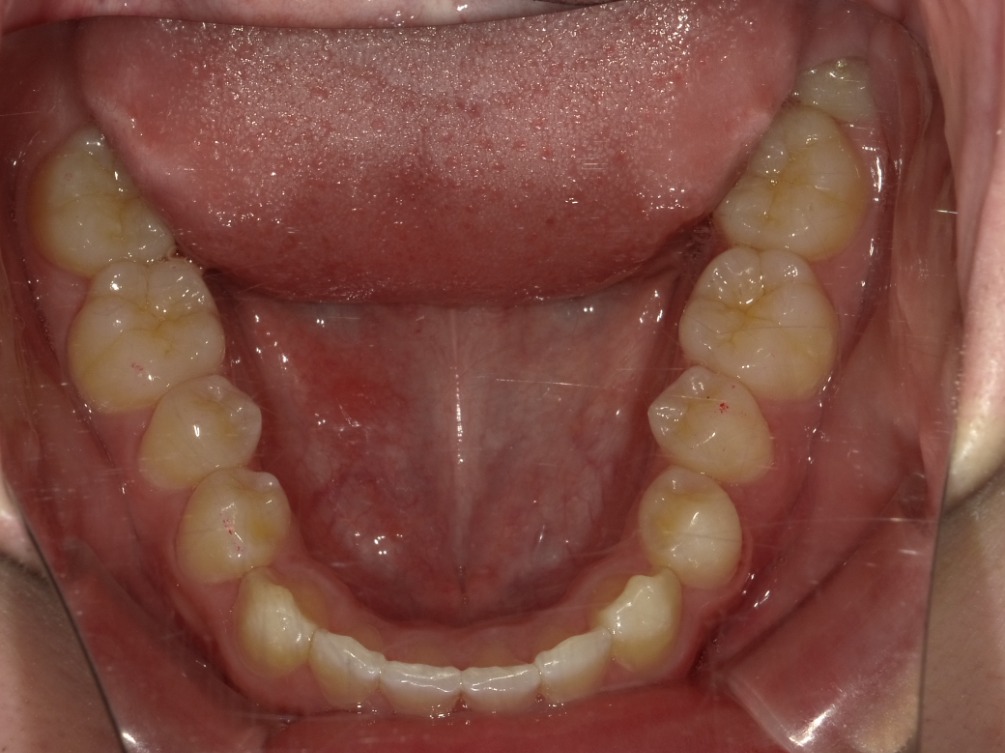

下顎

| 治療内容 | インビザライン 全顎 |

| 治療詳細 | 反対咬合や叢生を整えるために、歯の表面にアタッチメント(白い突起)をつけ、IPR(歯と歯の間を削る)を行いました。 また、顎間ゴムと呼ばれる上顎と下顎に渡って引っ掛けるゴムの補助装置も用いて治療を行いました。 |

| 患者情報 | 10代 男性 デンタルモニタリング使用 |

| 主訴 | 下顎が前に出ている(受け口) 歯のがたつき |